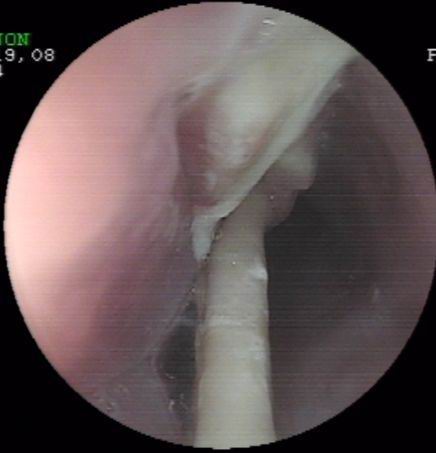

上個月末,一誤食異物(雞骨)胸骨后疼痛4天的患者經胃鏡檢查確診為食管異物嵌頓。因患者異物嵌頓時間長,且患者其間還采取了其它一些清除異物的方法,造成異物的兩端均刺入食管壁,刺入處食管粘膜糜爛,充血,腫脹。按常規(guī),該患者應收治外科行開胸手術取出術,但患者家境貧寒,且為家里主要勞力,無法承受醫(yī)療費用及開胸術后所造成暫時的勞動能力降低的損失。為減輕患者經濟負擔及痛苦,在確診食管異物尚未造成食管周圍重要臟器損傷的情況下,該室決定在胃鏡下試取,經多方面嘗試,最終成功將一長約3.6cm兩端鋒利的雞骨(圖示)行內鏡下取出,術后患者康復好,真正做到了微創(chuàng)手術解除患者大問題,減輕了患者經濟及軀體負擔。